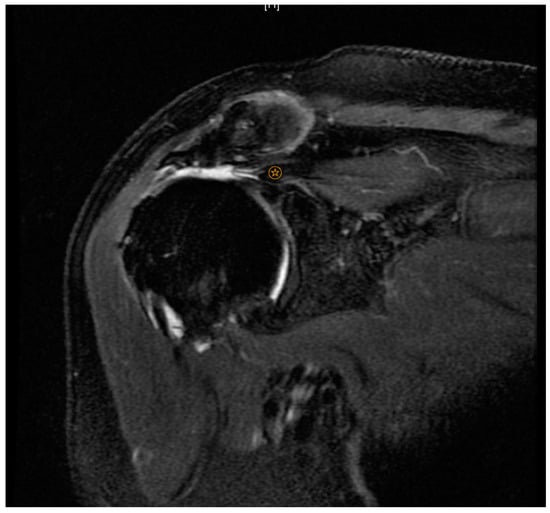

indicates level of supraspinatus tendon retraction.